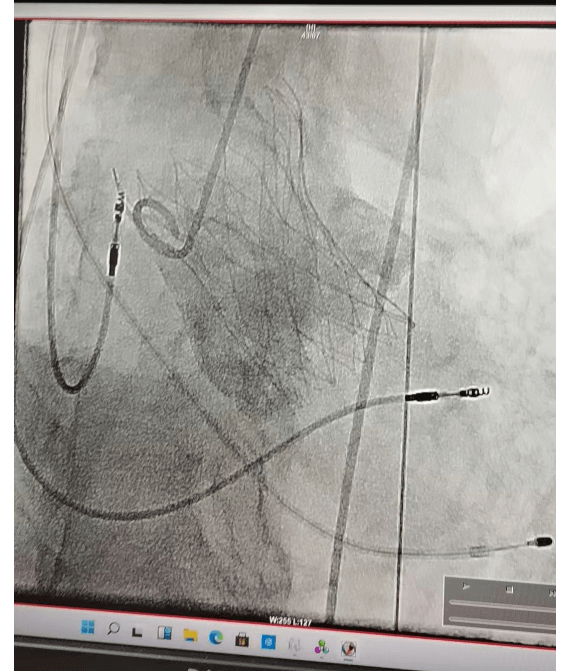

4月11日在全麻下行經(jīng)皮介入下主動脈瓣置換術(shù)。經(jīng)右側(cè)股動脈,在DSA引導(dǎo)下經(jīng)傳輸器將人工主動脈瓣膜送入主動脈瓣環(huán)內(nèi),定位準(zhǔn)確后逐步釋放人工瓣膜,完成瓣膜置換,術(shù)后超聲顯示人工瓣膜固定良好,無瓣周漏,無返流。手術(shù)歷經(jīng)約兩小時順利結(jié)束,超聲顯示,主動脈瓣跨瓣壓差基本消失,返流大大減輕。手術(shù)獲得成功,術(shù)后患者24小時下床活動,恢復(fù)良好出院!